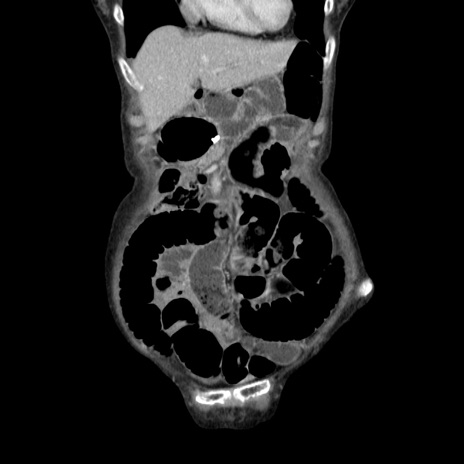

横断像